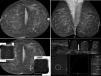

In the MRI and MG binomial, the most sensitive technique is MRI,9,12,13,15,16 regardless of age, risk group or breast density13 (Fig. 2). MG adds little to MRI and does not increase sensitivity much.12,13,16 Cancers detected by MG alone represent a very low percentage and are largely DCISs (and low-grade cancers).11,12 Several studies have reported that around 30% of cancers12,16,49 are detected by MRI alone (some studies have reported figures as high as 45%50 and 50%11). MG uses ionising radiation and has lower sensitivity. Furthermore, in young patients, calcifying DCISs are rare. Therefore, EUSOMA23 has maintained its recommendation not to introduce MG until age 35 and never before age 30, whereas the main American guidelines continue to recommend introducing MG at age 30.17,21,30

Case of cancer detected in a screening study in a 47-year-old BRCA2 patient. Pathological axillary lymph node detected on magnetic resonance imaging (MRI) and on post-MRI ultrasound with a fine-needle aspiration biopsy (FNAB) positive for malignant cells with findings of metastatic carcinoma and millimetric cancer (8mm) in the ipsilateral breast, only visible on MRI as a millimetric non-circumscribed pseudonodular focal enhancement between the lower quadrants. An MRI-guided biopsy yielded a result of “grade 2 infiltrating ductal cancer+moderate-grade ductal carcinoma in situ”. There was no mammographic translation of the cancer between the lower quadrants of the left breast (measuring 8mm) detected on MRI, despite the predominantly fatty density. This patient's previous breast MRIs, three and two years earlier, had been difficult to assess as a result of multiple enhancements due to breast-feeding, and there was no MRI study in the year before the diagnosis. (The patient was the only case at our centre with axillary macrometastases.) (A) Bilateral mammography, craniocaudal projections: “ACR A” breasts, with no obvious lesions (normal). (B) Bilateral mammography, mediolateral oblique projections. “ACR A” breasts, with no obvious lesions (normal). Axillary lymphadenopathy is partially seen on the left mediolateral oblique projection (arrow). (C) Mammographic focal compressions over asymmetries of outer quadrants of right breast and inner quadrants of left breast of baseline craniocaudal projections (arrows), which did not persist, leading to the deduction that these were areas of overlapping tissue. (D) Left axillary ultrasound (a): pathological left axillary lymphadenopathy, with widespread cortical thickening with FNAB: “positive for malignant cells with findings of metastatic carcinoma”. Breast ultrasound showed no obvious findings. Breast MRI with intravenous contrast: on delayed axial 3D with fat saturation (b) pathological axillary lymphadenopathy is seen (arrow), and on delayed 3D axial with fat saturation (c) non-circumscribed pseudonodular focal enhancement measuring 8mm in the lower quadrants of the left breast is seen (circle); early digital subtraction (d): non-circumscribed pseudonodular focal enhancement measuring 8mm in the lower quadrants of the left breast (circle); uptake curve (e): type 1 (this was the only obvious intramammary enhancement, arousing suspicion of malignancy); and MRI-guided vacuum-assisted biopsy, 3D axial with fat saturation (e): non-circumscribed pseudonodular focal enhancement measuring 8mm between the lower quadrants of the left breast with no ultrasound translation subjected to an MRI-guided biopsy, with a result of “grade 2 infiltrating ductal carcinoma+moderate-grade ductal carcinoma in situ”. Molecular subtype: luminal B.